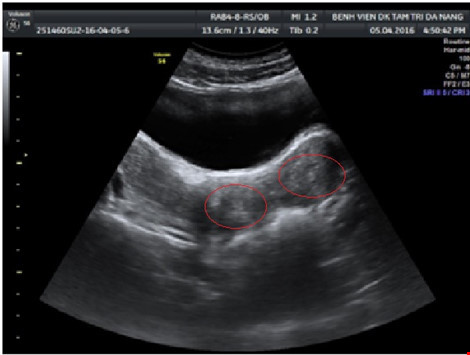

Bé gái có 2 tử cung, 2 âm đạo nhưng có 1 âm đạo không thông với màng trinh dẫn đến việc ứ máu khi đến tháng, gây đau bí tiểu và táo bón.